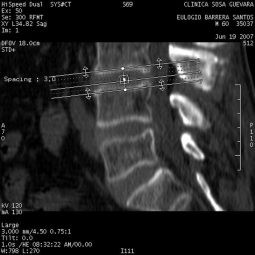

Clínica de Radiología y Ultrasonografía Sosa - Guevara

TAC de columna vertebral

Clinicas > Radiologia

VER GALERÍA